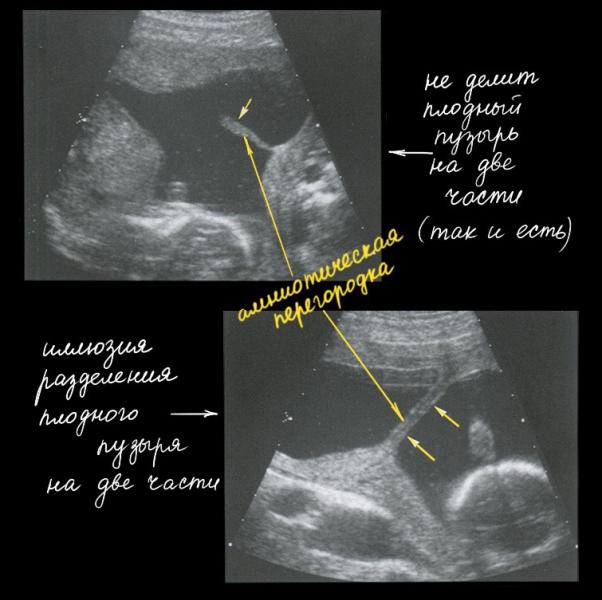

Амниотическая перегородка никогда не разделяет плодный пузырь на две части, хоть на УЗИ в определенных срезах может так показаться. И самое главное, амниотическая перегородка в отличие от амниотических тяжей никогда не прикрепляется к плоду, а значит не приносит ему никакого вреда. Иногда даже плацента может лежать на этой перегородке.